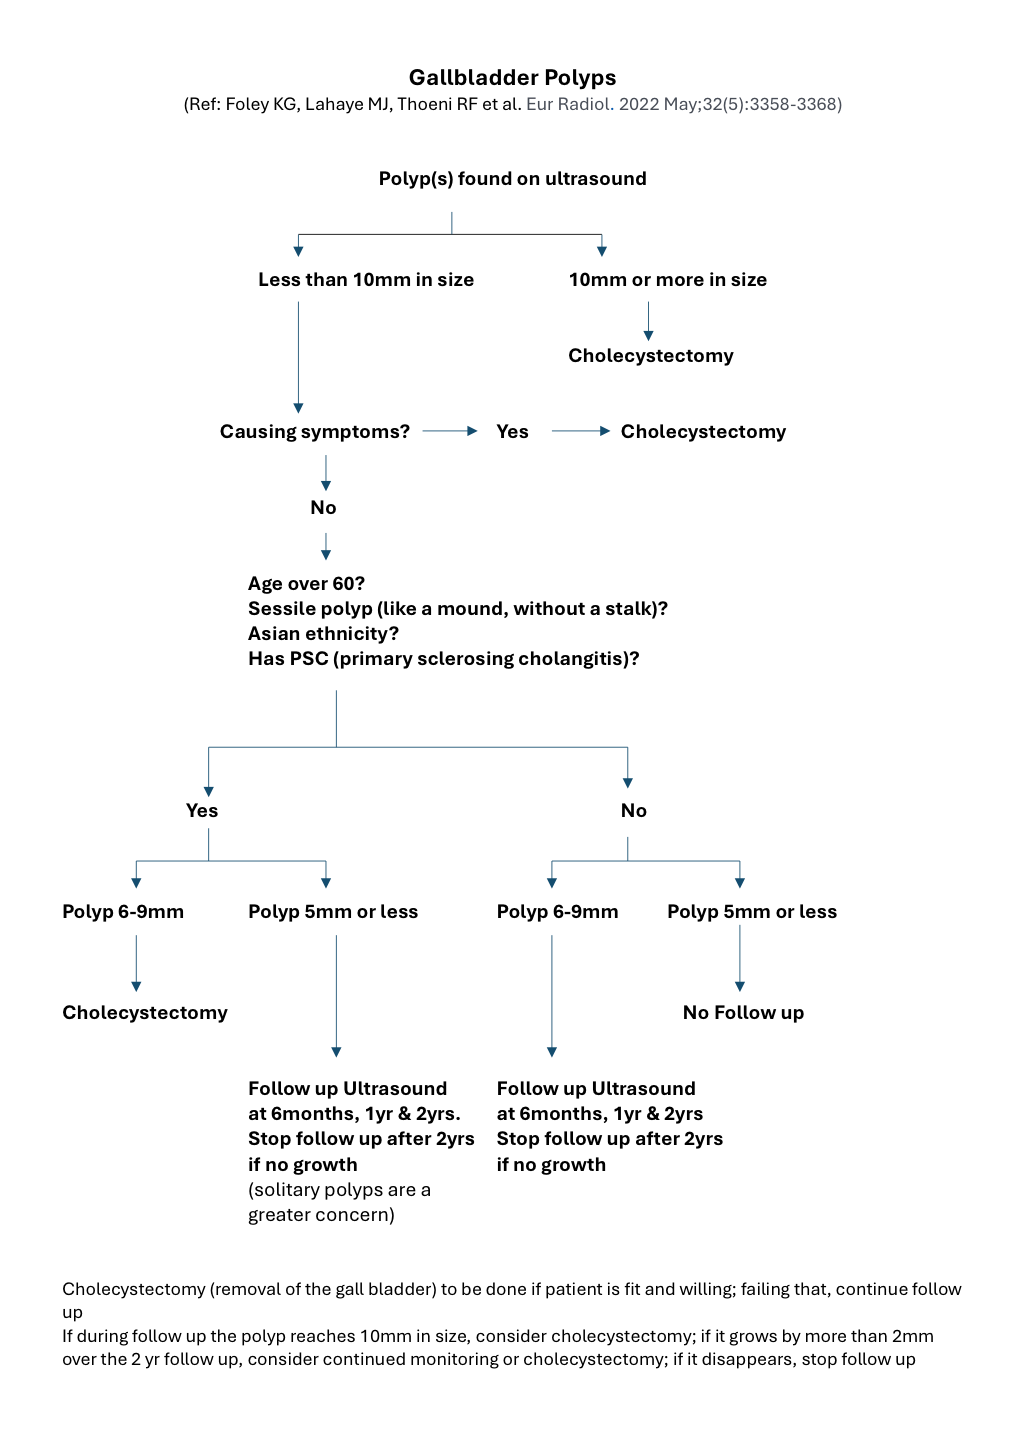

Polyps that are 1 cm or more in diameter should be deemed as suspicious i.e. they may develop or are developing into cancerous (malignant) growths. Also, polyps that have developed in older patients (over the age of sixty years), developed in association with stones or are associated with symptoms, or have a sessile shape (i.e. heaped up, without a stalk) are at a higher risk of being malignant or subsequently turning malignant. Asian ethnicity and the presence of a condition called Primary Sclerosing Cholangitis (PSC) are also thought to increase the risk. Laparoscopic cholecystectomy (keyhole surgery to remove the gall bladder) is the treatment of choice in these patients, unless the suspicion of malignancy is very high, in which case open exploration is preferable, with preparation for extended resection if necessary.

Polyps that are 1 cm or more in diameter should be deemed as suspicious i.e. they may develop or are developing into cancerous (malignant) growths. Also, polyps that have developed in older patients (over the age of sixty years), developed in association with stones or are associated with symptoms, or have a sessile shape (i.e. heaped up, without a stalk) are at a higher risk of being malignant or subsequently turning malignant. Asian ethnicity and the presence of a condition called Primary Sclerosing Cholangitis (PSC) are also thought to increase the risk. Laparoscopic cholecystectomy (keyhole surgery to remove the gall bladder) is the treatment of choice in these patients, unless the suspicion of malignancy is very high, in which case open exploration is preferable, with preparation for extended resection if necessary.

For polyps that are deemed low-risk, our practice is to recommend follow-up at first with ultrasound scans at 6 months, 1 year and 2 years.

Please see below for a more detailed flow chart.